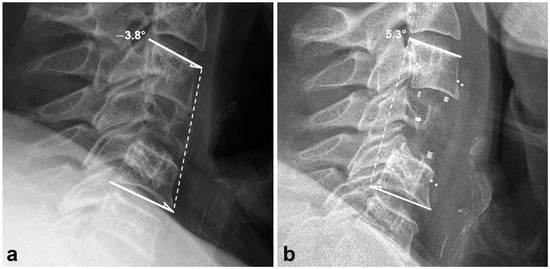

3.2. Radiologic Outcomes